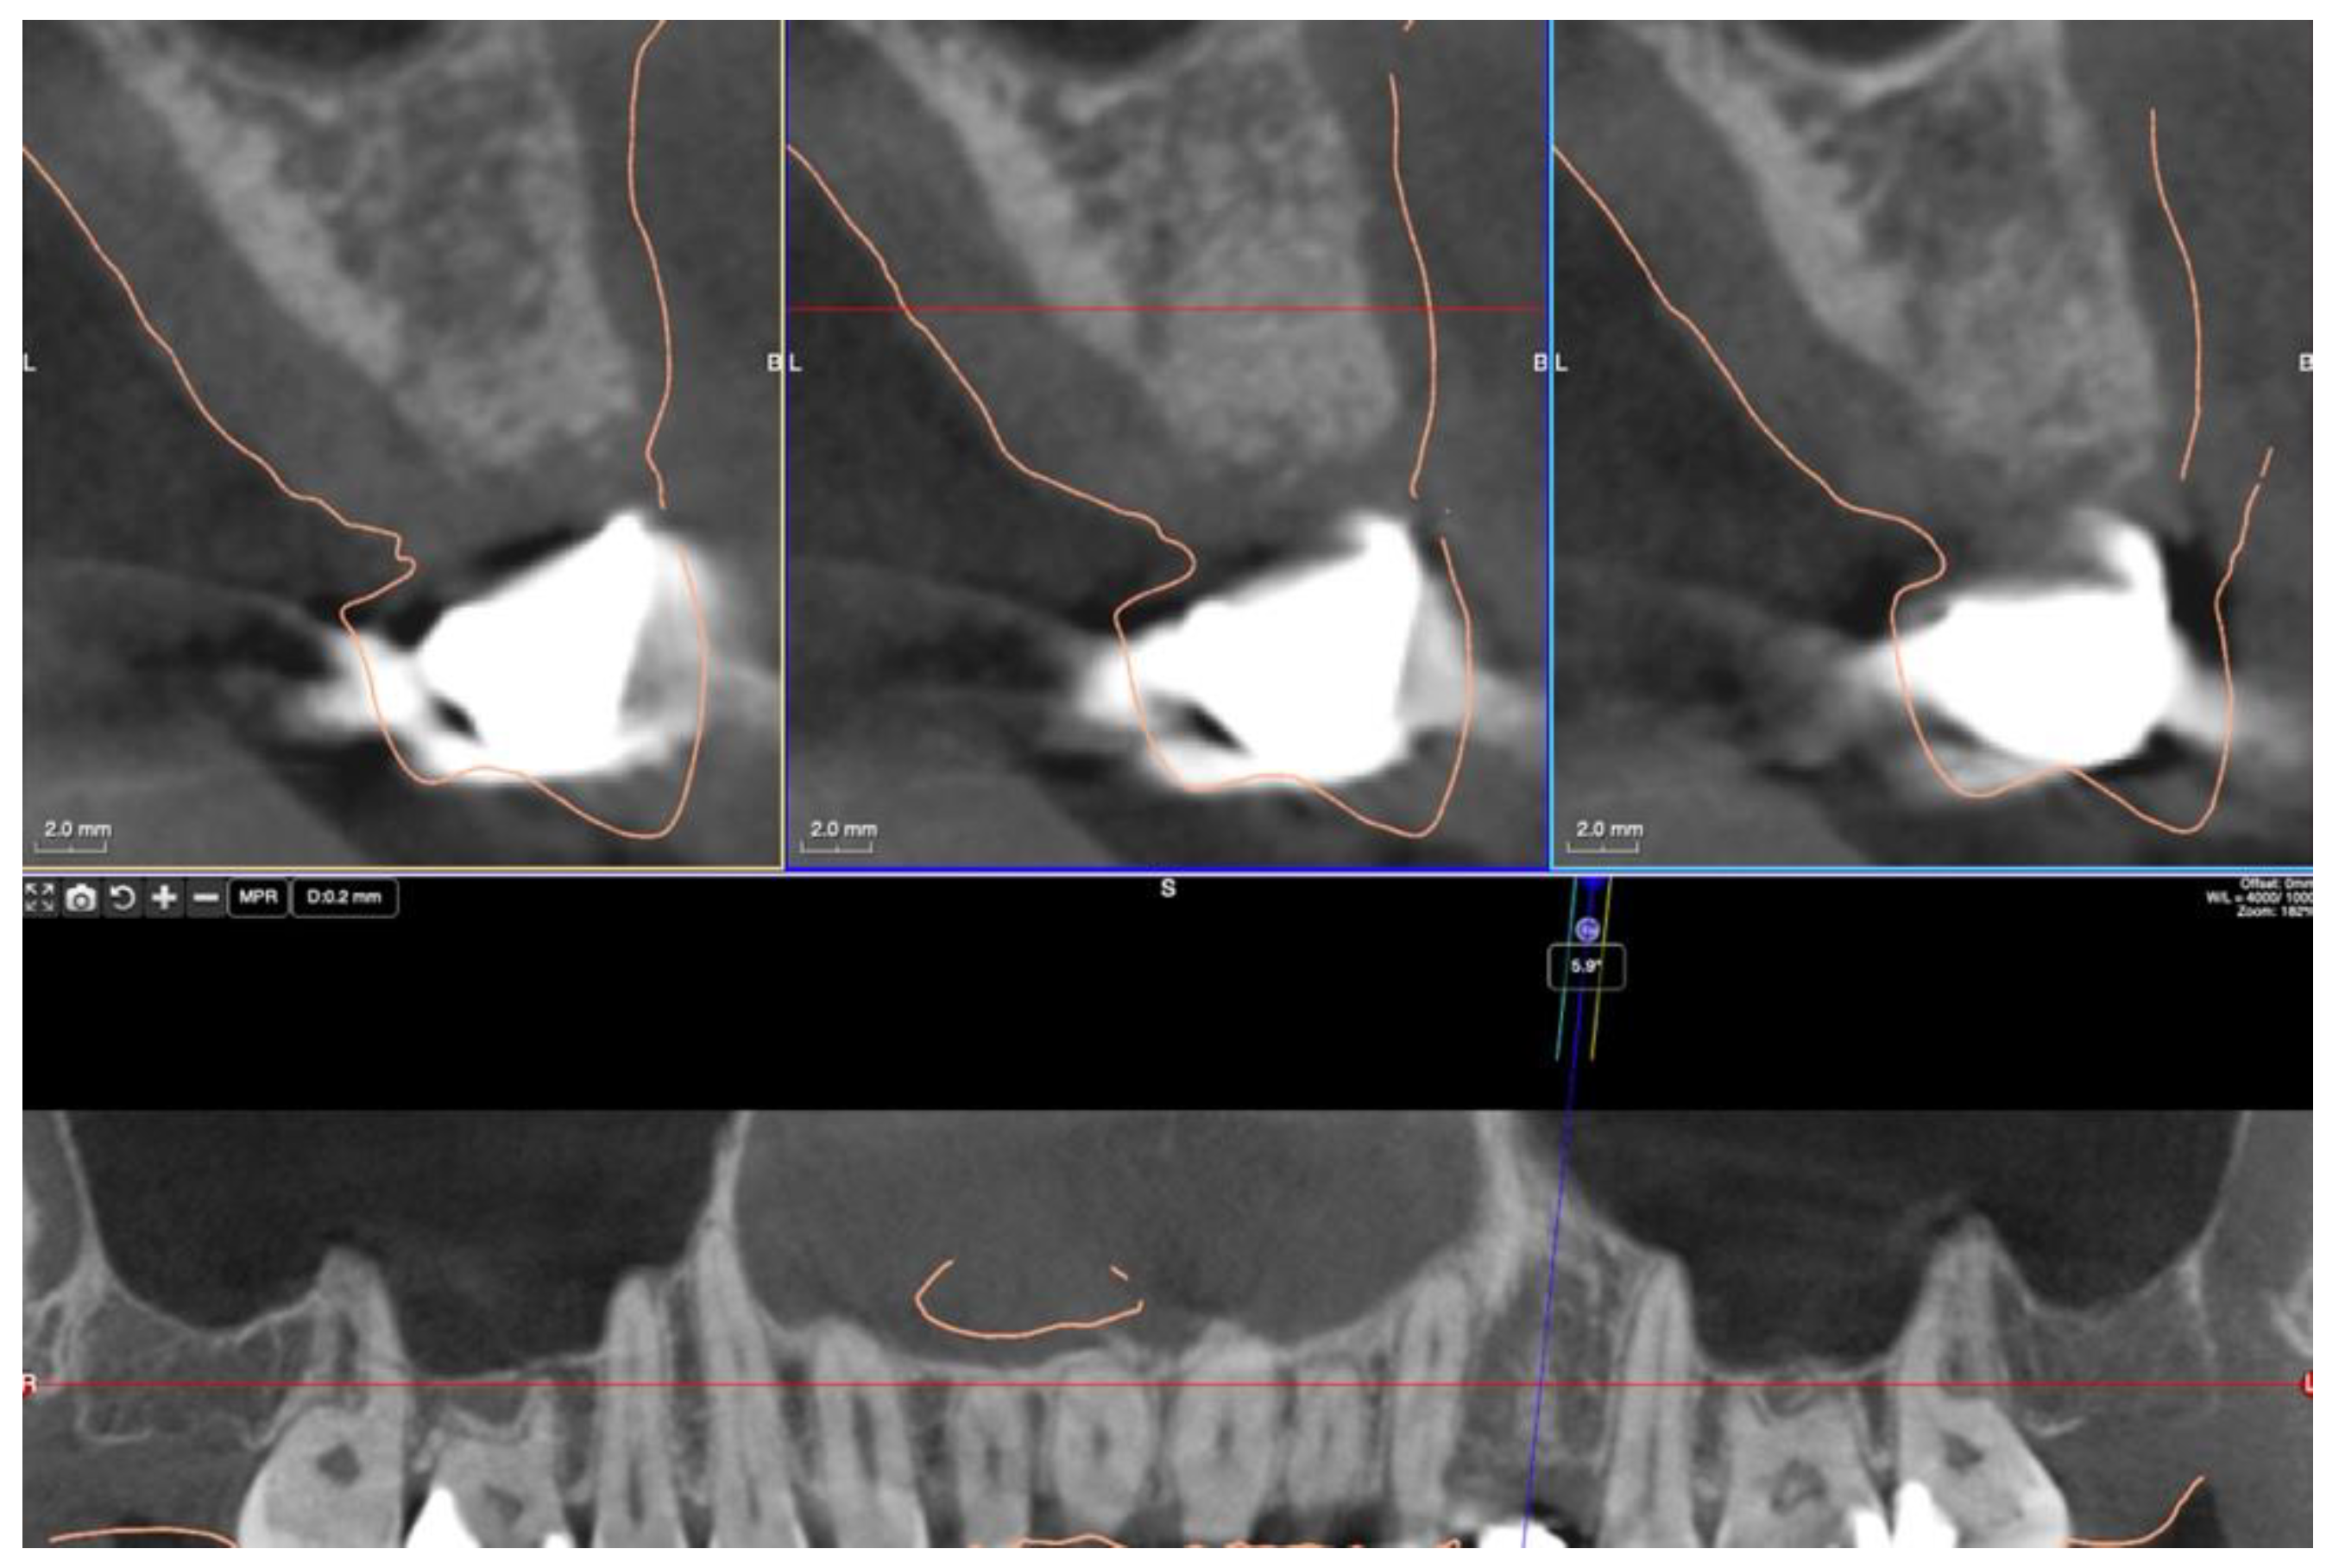

2. Materials and Methods

3.2. Ridge Dimension